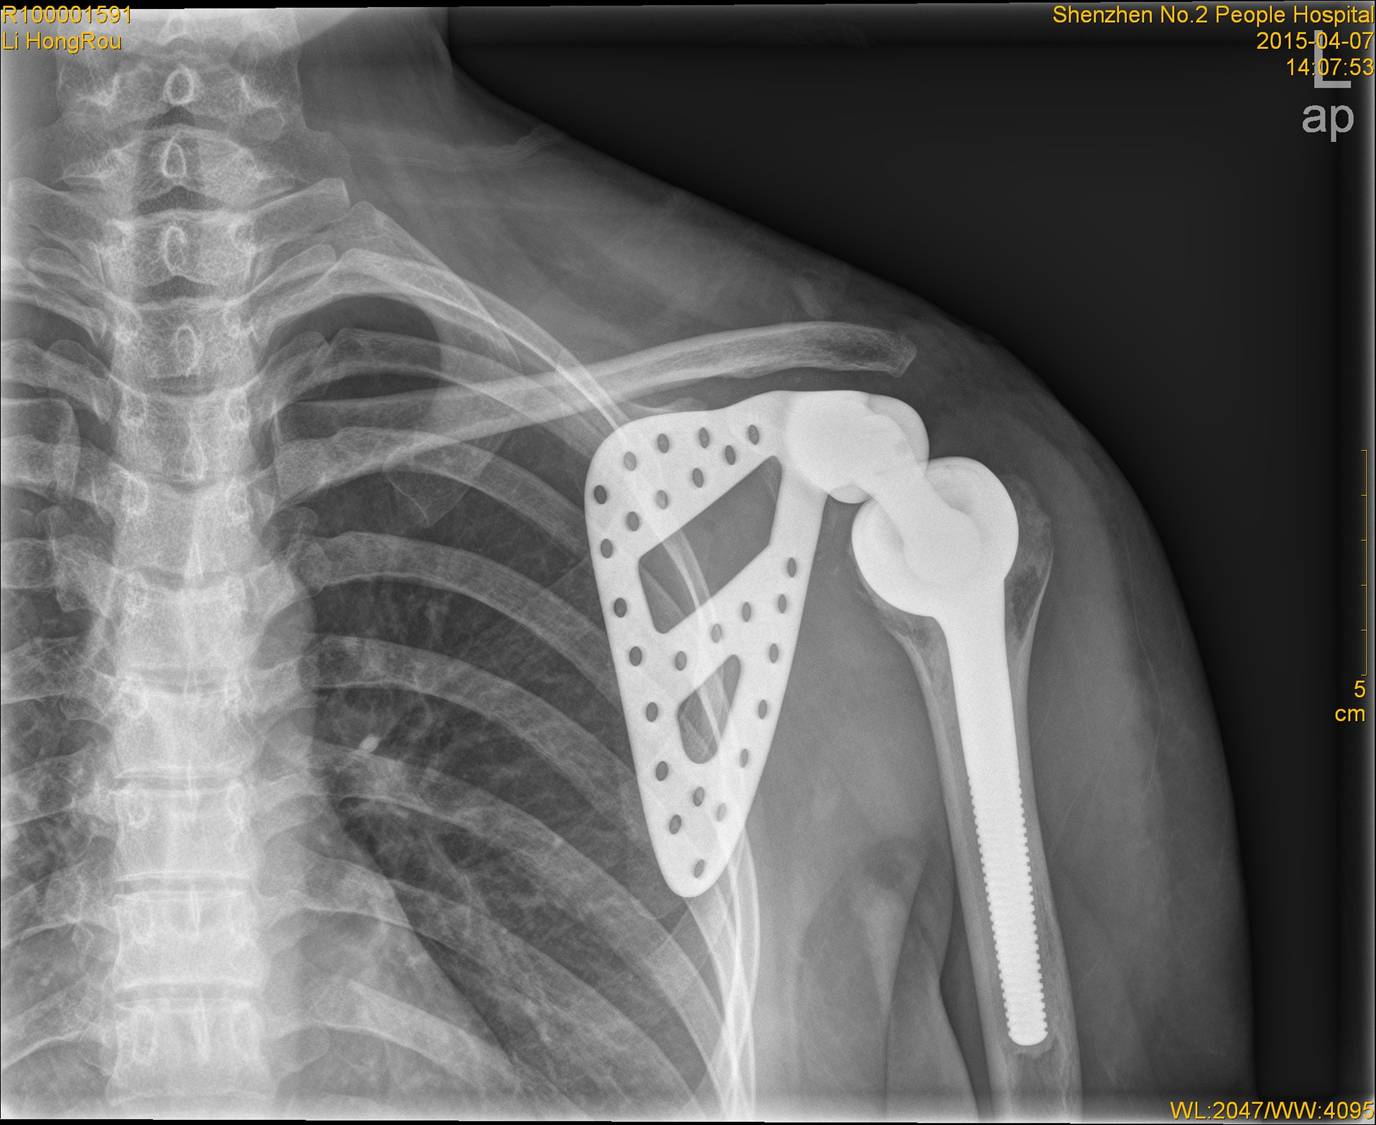

В Китае успешно проведена операция по протезированию лопатки, c участием 3D-технологии печати.

Болезнь за короткое время распространилась на 75% кости. При таких обстоятельствах пациенты во время лечения теряют руку. Но не в этот раз. Китайским врачам удалось напечатать и имплантировать китайской девушке точную копию сустава.

Для того чтобы создать титановый протез, специалисты использовали снимки компьютерного томографа и создали в 3D-редакторе точную реплику лопатки девушки. Затем пластиковую модель напечатали на 3D-принтере и отправили в специальный цех для изготовления полноценной титановой копии.

Операция прошла успешно, все мышцы срощены, и сейчас Ли проходит реабилитацию. Через 6 месяцев врачи обещают полное восстановление руки.